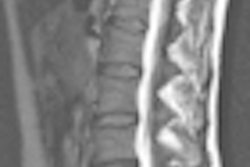

- MRI brain scans for the diagnosis of brain cancer